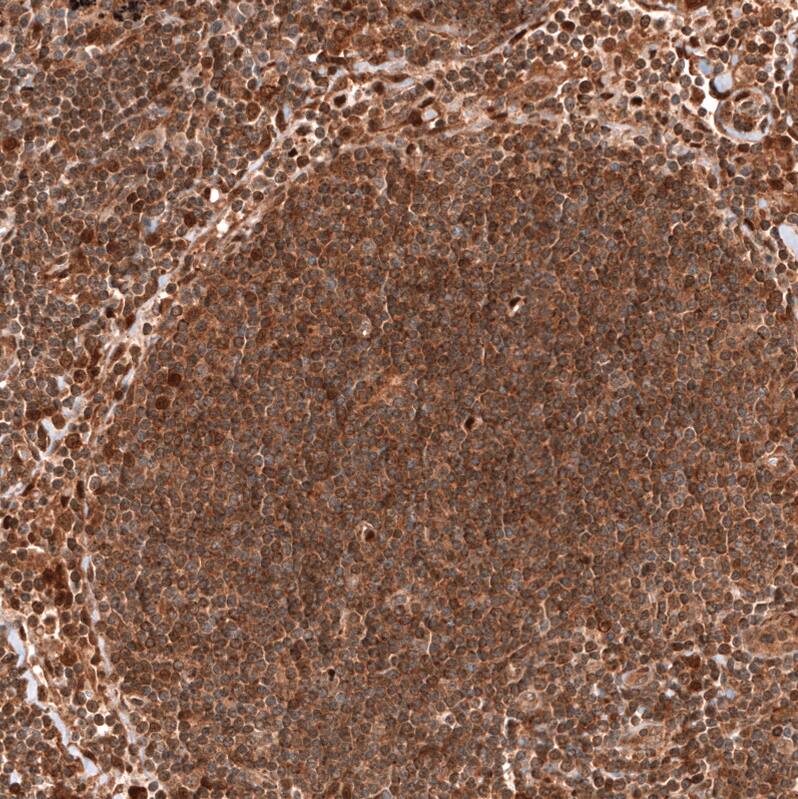

PTEN Antibody (CL11722) - Azide and BSA Free Immunohistochemistry-Paraffin: PTEN Antibody [NBP3-44313]

Immunohistochemistry-Paraffin: PTEN Antibody [NBP3-44313]

Analysis in human lymph node and skeletal muscle tissues using NBP3-44313 antibody. Corresponding PTEN RNA-seq data are presented for the same tissues.